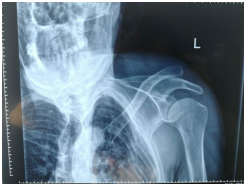

5月21日下午16時(shí)46分,又一位意外受傷患者劉某由輪椅推入我科。據(jù)悉患者因在自家勞作時(shí)從約兩米的高處摔落,患者傷后發(fā)生短暫昏迷,后經(jīng)通知家人急診收入我院骨科,通過(guò)詢問(wèn)病史及完善相關(guān)檢查后,劉某確診為多發(fā)性肋骨骨折及左肩鎖關(guān)節(jié)脫位,應(yīng)盡快予以手術(shù)減輕病痛。在征得患者及家屬同意手術(shù)的情況下,手術(shù)順利完成,患者目前各項(xiàng)生命體征平穩(wěn),現(xiàn)于外科病房接受進(jìn)一步的觀察與治療。